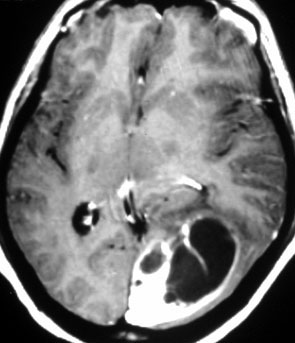

1984年 19歳の時に,松果体のジャーミノーマに全脳照射45グレイで治療されました(左CT)。1997年左蝶形骨縁にヘマンジオペリサイトーマが発生しました(中央と右のMRI)。手術で全摘出しましたが4年後,2001年に脊髄に播種再発してつらい経過を辿りました。眼窩壁を破る典型的なヘマンジオペリサイトーマの像で,放射線誘発髄膜腫との鑑別がとても大切なものです。

左側の画像は照射後再発を手術摘出後です,数ヶ月で再燃しています,かなり早い増殖速度で再発してきて取りきれません